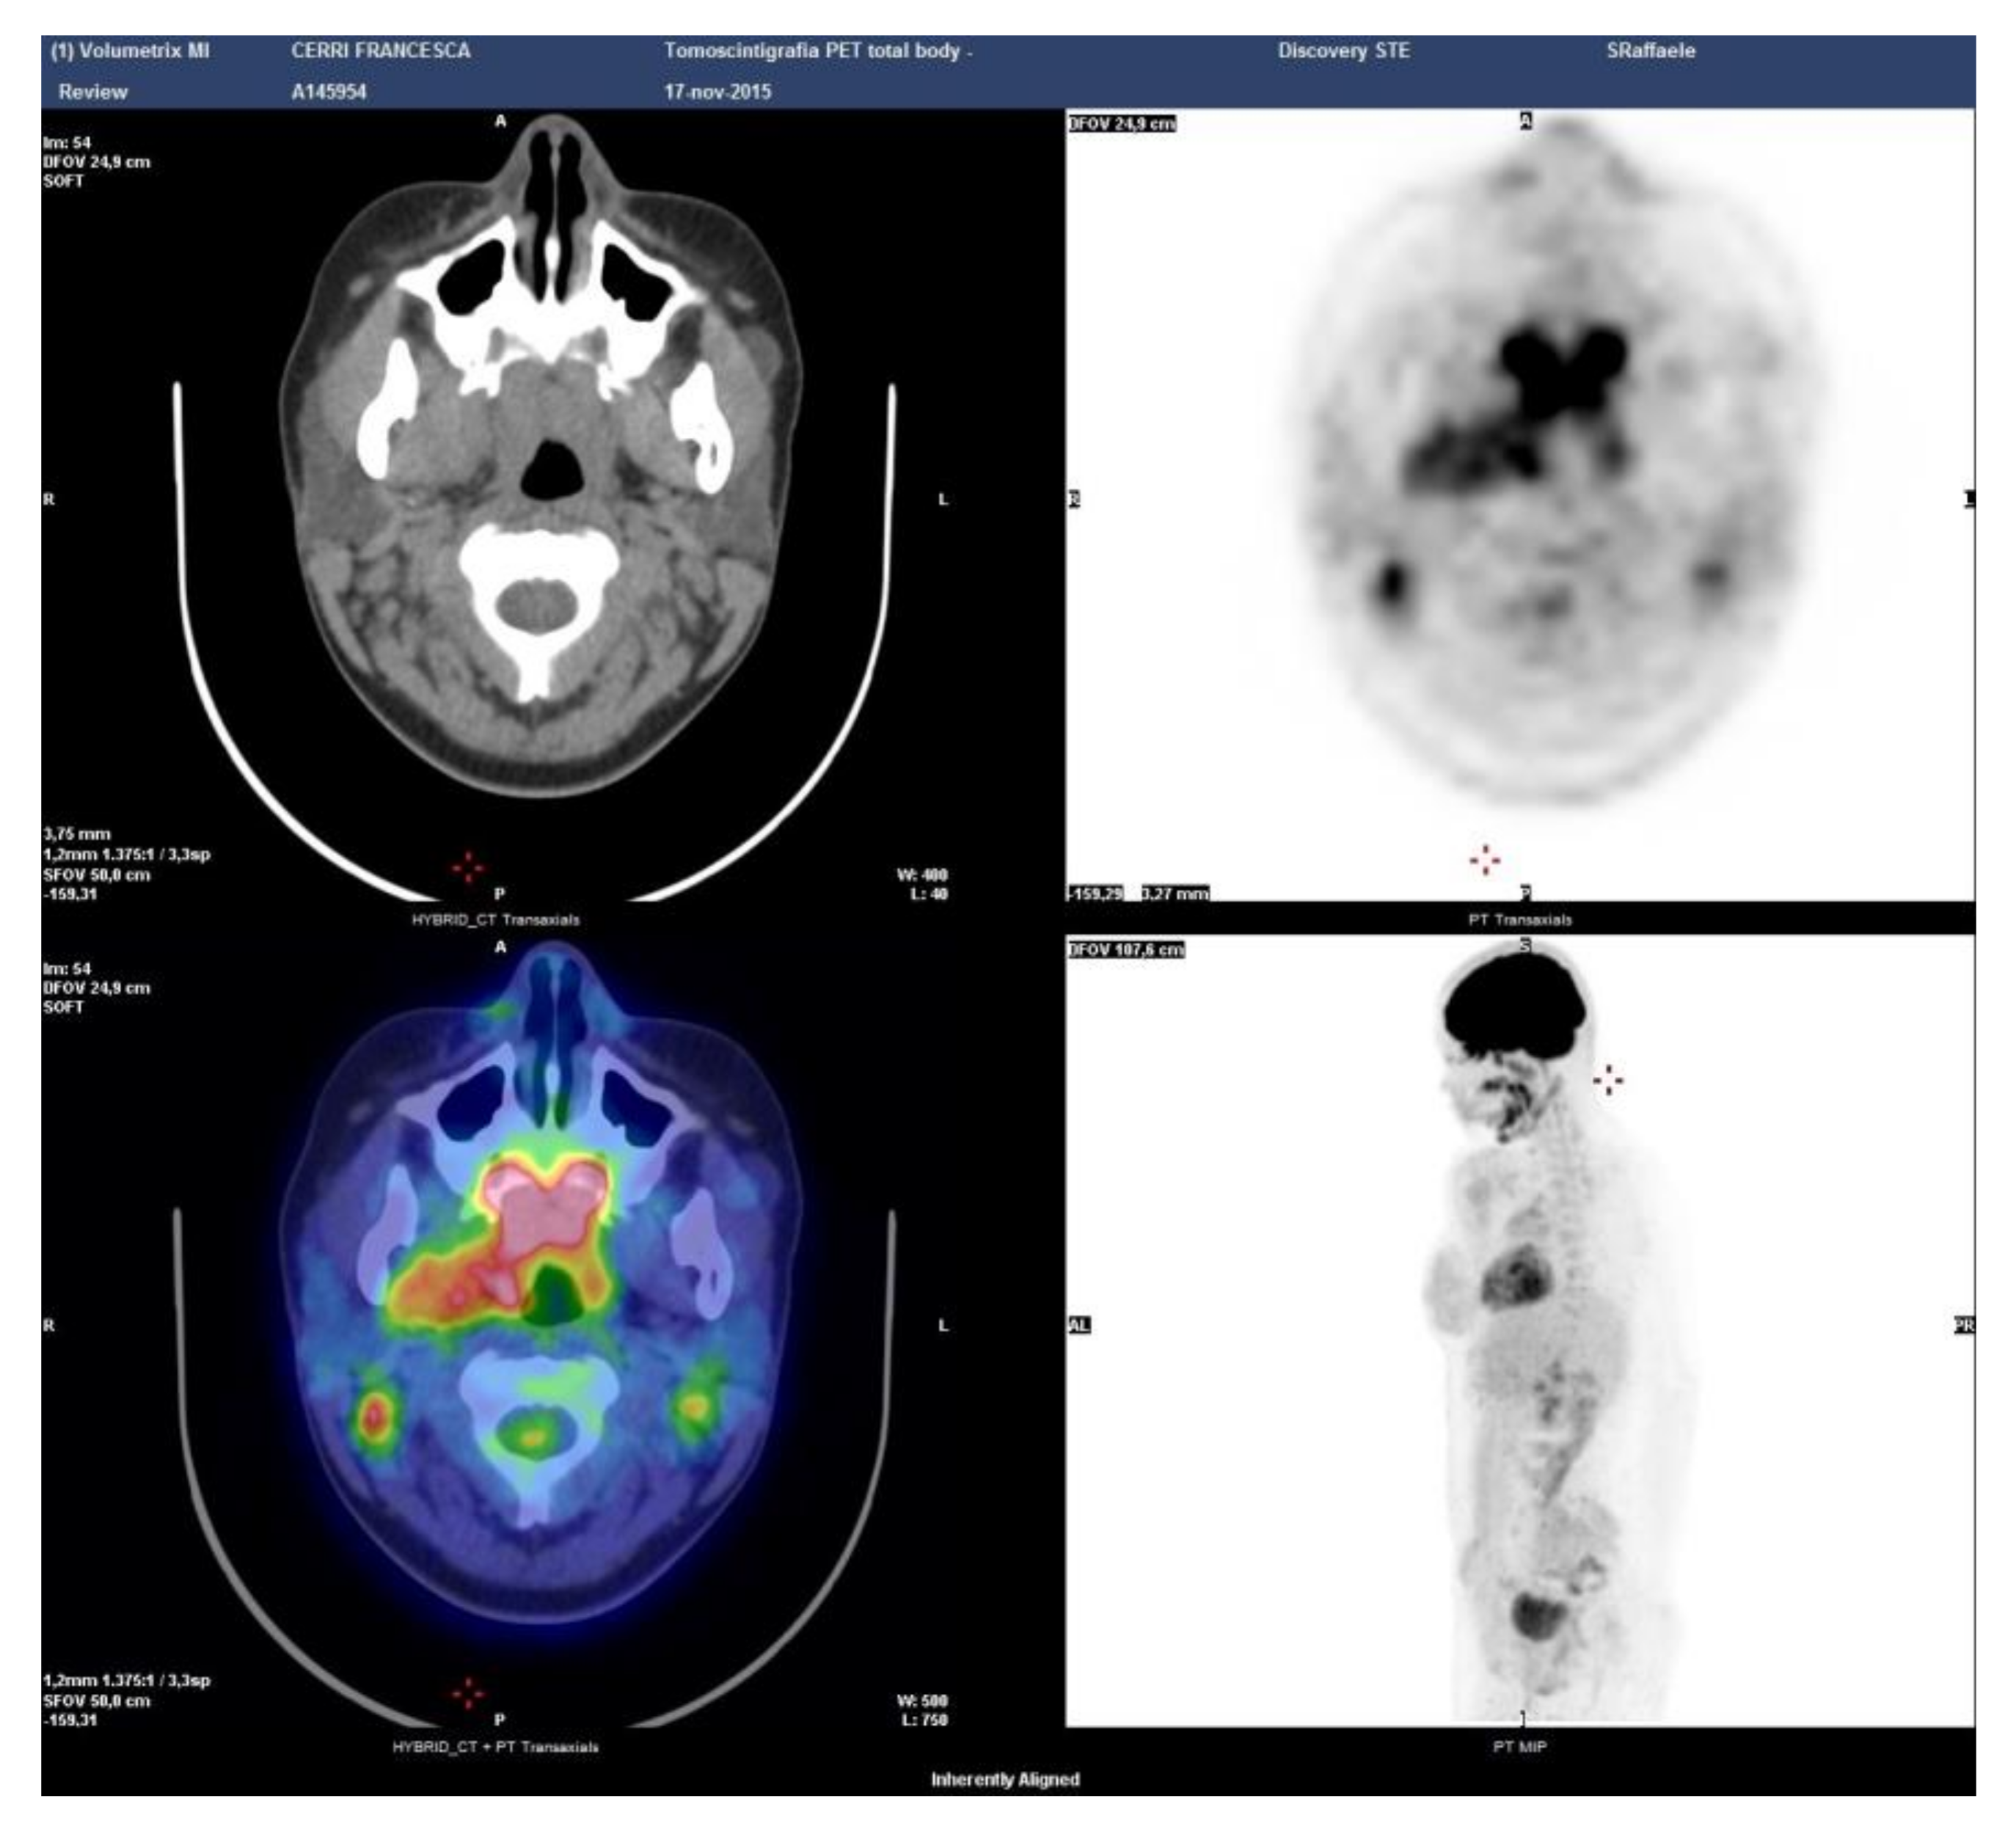

| 2 | 20, F | Hard palate | Cervical lymph nodes, parotids, oropharynx, pterygopalatine fossa | 5 | 0.3 | 421 |

| 2 | Small salivary gland: fibrosis, IgG4+ 50 × HPF, IgG4+/IgG+ plasma cells 70% | Rituximab 375 mg/m2, four weekly infusions IV. Prompt resolution of symptoms. | |